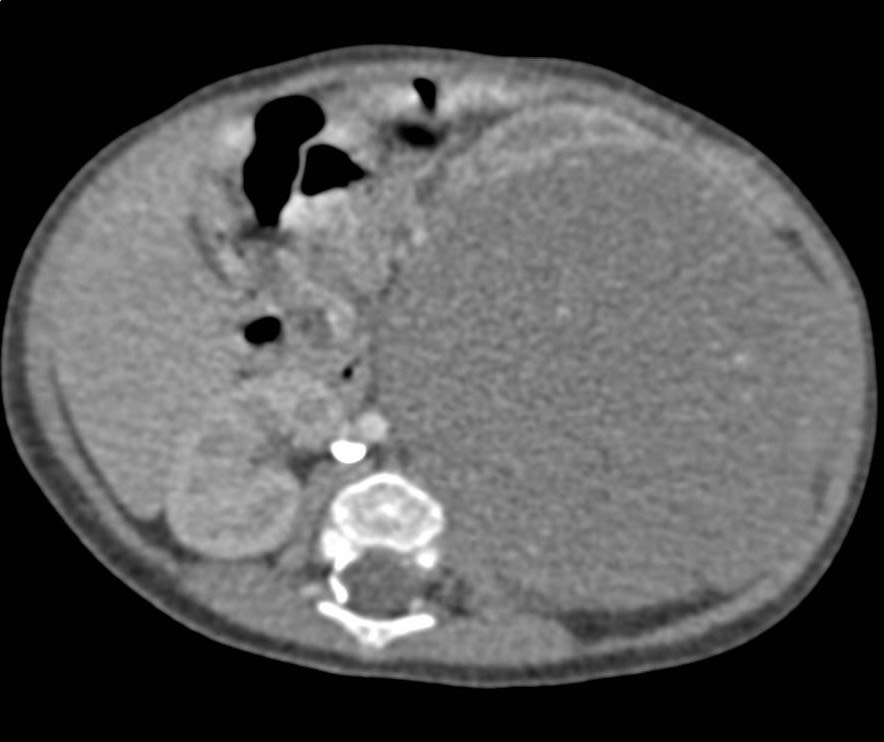

2961. Ребенок двух лет со случайной находкой в ходе планового осмотра, выполнена компьютерная томография, рентгенологическая картина соответствует